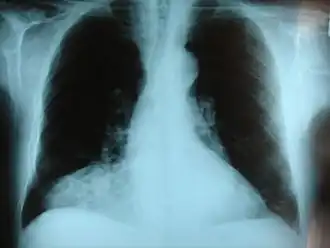

O hernie este o umflătură formată prin ieșirea anormală a țesutului sau a unui organ, cum ar fi intestinul, prin peretele cavității în care se află în mod normal.[1] Herniile sunt de mai multe tipuri.[2] Cel mai frecvent ele apar în abdomen, în special în zona vintrelor.[2] Herniile abdominale sunt cele mai frecvente, putând fi inghinale sau femurale.[1] Alte hernii includ herniile hiatale, incizională și ombilicale.[2] Simptomele sunt prezente la aproximativ 66% dintre persoanele cu hernii inghinale.[1] Acestea pot include dureri sau disconfort mai ales cu tuse, dureri la efortul fizic sau nevoia de a merge la baie.[1] Ea se agravează de multe ori de-a lungul zilei și se ameliorează atunci când persoana stă culcată.[1] Poate să apară o zonă bombată, care devine mai mare atunci când atârnă în jos. Herniile abdominale apar mai frecvent pe partea dreaptă decât pe stânga.[1] Principala îngrijorare este strangularea, în cazul în care este blocată alimentarea cu sânge a unei părți a intestinului.[1] Aceasta produce, de obicei, dureri severe și o sensibilitate a zonei.[1] Herniile hiatale duc de multe ori la arsuri la stomac, dar pot provoca, de asemenea, dureri în piept.[3]